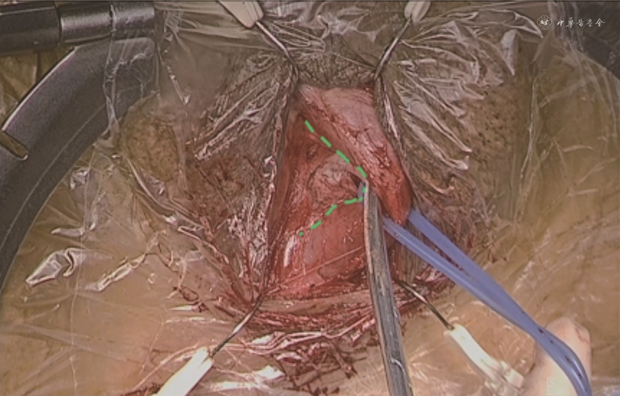

2. 手术方式:AUS植入术的手术及尿道压力描记过程详见相关研究的报道[4, 5, 6, 7]。传统尿道分离方式为逐层分离皮下组织,显露尿道海绵体,自尿道海绵体背侧环形游离尿道后测量尿道周径(图1),进而选择袖套尺寸。而本研究采用的改良尿道分离方式,为在游离尿道海绵体背侧时,借用部分海绵体白膜组织(推荐距离尿道海绵体侧壁5~10 mm处开始进行尿道背侧的游离,图2),使其附着于尿道背侧,后合并测量周径并选择合适袖套植入。改良尿道分离方式及袖带放置的具体位置见图3。